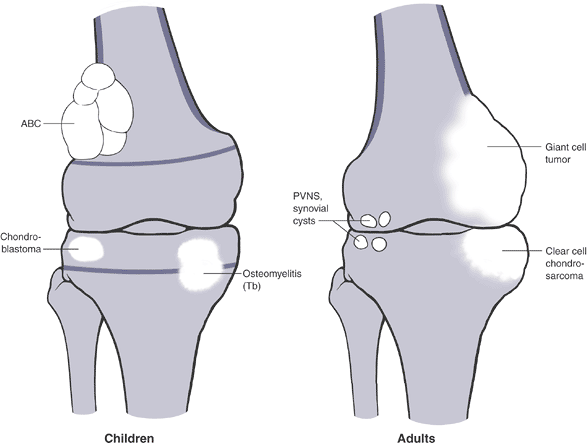

Epiphyseal lesions. Lesions of the

epiphysis may either be isolated to one side of the joint or involve

both sides. The differential diagnosis differs for these two general

groups, although for those lesions

P.12P.13P.14P.15P.16P.17P.18P.19P.20P.21P.22P.23

that

may involve both sides of the joint, an isolated lesion early on in the

disease process may involve only one side. PGCAT is a convenient

mnemonic to recall the most common lesions in both of these categories,

but it does not distinguish between lesions that are always solitary

and those that may involve one or both sides of the joint (Figs. 1-14 and 1-15 and Box 1-5).

Figure 1-14

PGCAT lesions. Epiphyseal lesions have a relatively narrow differential

diagnosis that can be recalled using the mnemonic PGCAT, which includes

such common epiphyseal lesions as PVNS (pigmented villonodular

synovitis), GCT (giant cell tumor of bone), chondroblastoma, ABC

(aneurysmal bone cyst), and Tb (tuberculosis). In the figure, the femur

on the left, with open growth plates shown, illustrates common

pediatric epiphyseal lesions. Chondroblastoma is represented by the

purely epiphyseal radiolucency without sclerotic borders. Aneurysmal

bone cyst is represented by the septated, expansile lesion centered in

the meta-epiphysis. Osteomyelitis, of which tuberculosis is only a

representative example, may manifest itself as a metaphyseal

radiolucency eroding across into the epiphysis, as shown on the

pediatric figure. The femur on the right, without open growth plates,

illustrates the common adult epiphyseal lesions. Synovial processes, of

which PVNS is only a representative example, are relatively common.

Degenerative geodes and intraosseous ganglions are more common examples

of such processes. Giant cell tumor of bone has its epicenter in the

metaphysis but classically erodes down to subchondral bone within the

epiphysis.P.25

Figure 1-15 Bone lesions that frequently occur in the epiphyseal region. (A) Pigmented villonodular synovitis may show juxta-articular erosions. (B) Giant cell tumor of bone frequently extends from the metaphyseal region into the epiphysis and down to subchondral bone. (C) Chondroblastoma has its epicenter within the epiphysis and extends into the metaphysis occasionally. (D)

Most commonly, when aneurysmal bone cyst is seen in the epiphysis, it

occurs as a secondary lesion within a chondroblastoma or giant cell

tumor, although the lesion shown was a primary aneurysmal bone cyst

extending into the epiphysis.